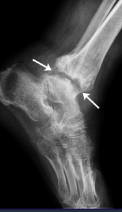

Arthrosis Rx

GENERAL Rx signs

Joint space narrowing (even or uneven)

Subchondral OS

Subchondral cysts

Osteophytes

Technique: 2 views AP + prophyle

CHANGES

Joint space narrowing : slow, expressed in %

Osteophytes: marginal, subcartilaginous

Subchondral OS & subuxation

Synovitis: joint effusion (US, MRI)